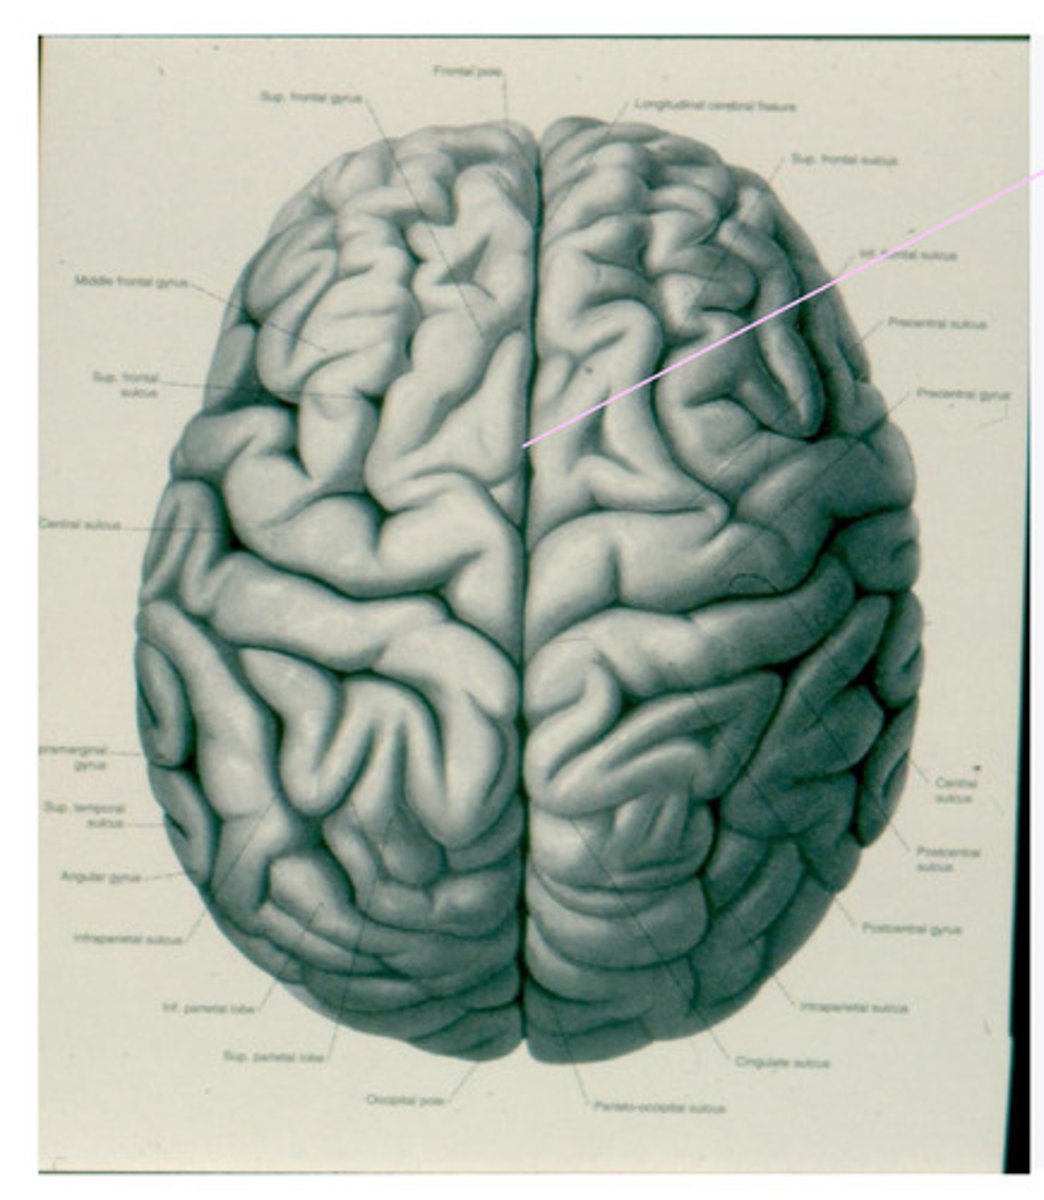

geri, sulci, lobes

What are the anatomical divisions of the cortex of the brain?

-frontal

-parietal

-temporal

-occipital

What are the 4 lobes of the brain?

central sulcus

What sulcus differentiates the frontal from the parietal lobe?

lateral sulcus

-precentral gyrus

-superior frontal gyrus

-middle frontal gyrus

-inferior frontal gyrus

-post-central gyrus

-superior parietal lobule

-inferior parietal lobule

What are the divisions of the parietal lobe?

-supramarginal gyrus

-angular gyrus

What are the divisions of the inferior parietal lobule?